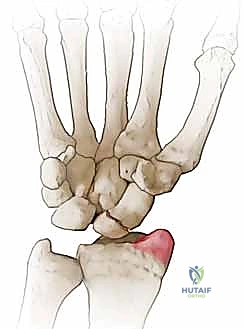

- المرحلة الأولى (Stage I): خشونة وتآكل في المفصل بين القطب البعيد للعظم الزورقي وعظم الكعبرة (الناتئ الإبري الكعبري).

تُعد عملية استئصال القطب البعيد للعظم الزورقي (Excision of the Distal Pole of the Scaphoid) حلاً جراحياً ذكياً ومبتكراً. الفكرة الميكانيكية وراء هذه الجراحة هي: "إذا كان القطب البعيد للعظم الزورقي هو الذي يحتك بعظم الكعبرة ويسبب الألم والخشونة، فلنقم بإزالته مع الحفاظ على باقي هياكل الرسغ".

- الاستئصال الدقيق: باستخدام أدوات جراحية ميكروسكوبية دقيقة، يتم استئصال حوالي 3 إلى 4 مليمترات من القطب البعيد للعظم الزورقي. هذه الكمية كافية لمنع الاحتكاك مع عظم الكعبرة، وفي نفس الوقت تحافظ على استقرار الأربطة.